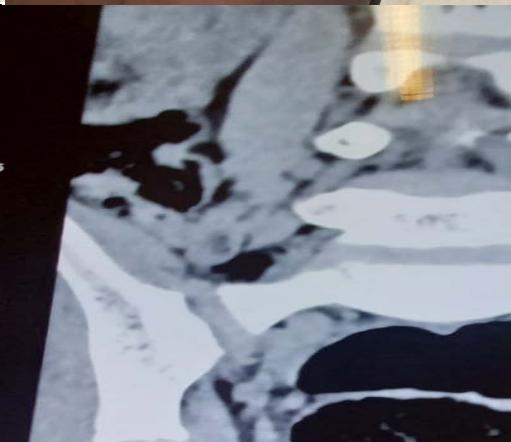

CT lumbar spine

Hypertrophy of the left L4 root of $12.8 \, \text{mm}$ in probable conflict with the disc which could evoke neurofibromatosis.

The scanner revealed hypertrophy of the left L4 root of $12.8 \, \text{mm}$ in probable conflict with the disc